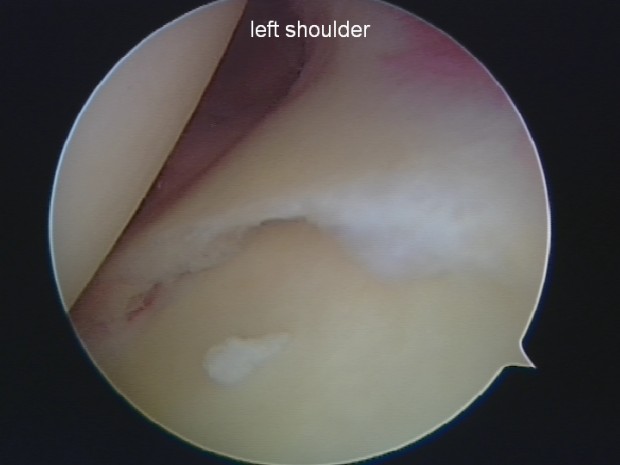

Bankarts Lesion, the upper left of the picture is Dan’s humeral head, directly underneath you can see the tear.